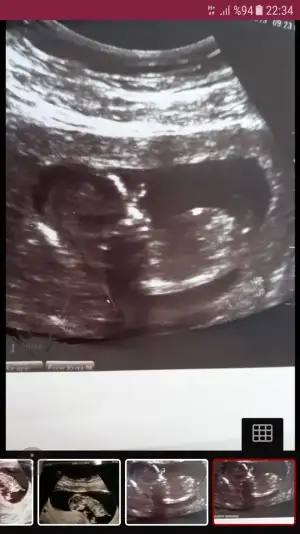

Kizlar cinsiyet tahmininiz varmi dr 12 hafta kiza benzetti 13 hafta baska dr yuzde 55 kiz gibi ama tam goremedim dedi ruyamda oglum olursa adini hamza yilmaz koyucam diyorum hep erkek hissettim ama kizada alistim hayirli saglikli olsun en basta tabiki cuma gunu kontrolum var dr kesinlesir dedi sizin tahminlerinizide alabikirmiyim ilk ikisi 12+digeri 13 haftalik

Eklentiler

• Screenshot_20190630-010258.webp

Screenshot_20190630-010258.webp

17,9 KB · Görüntüleme: 191

• Screenshot_20190704-182556_Samsung Internet.webp

Screenshot_20190704-182556_Samsung Internet.webp

27,1 KB · Görüntüleme: 197

• Screenshot_20190628-223445.webp

Screenshot_20190628-223445.webp

28,8 KB · Görüntüleme: 171